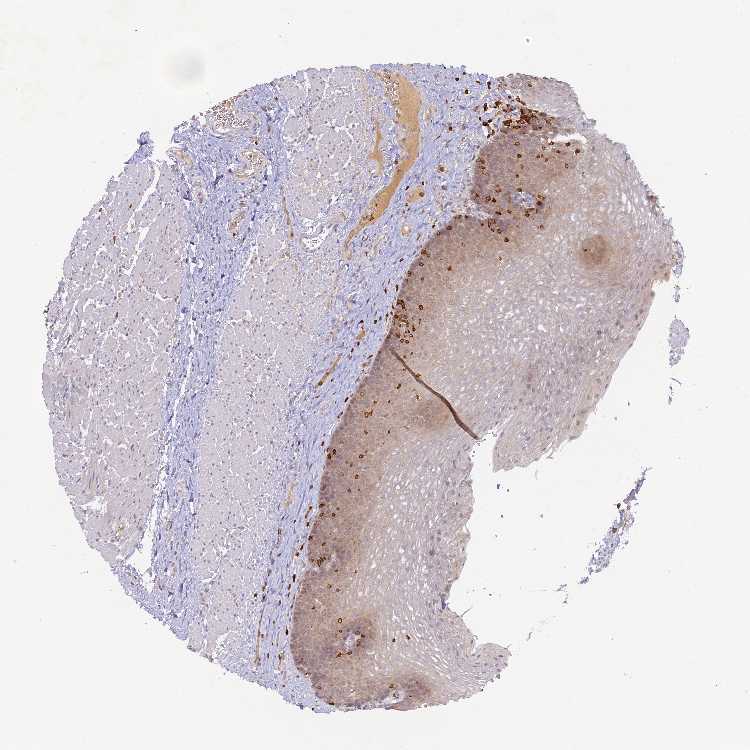

ESOPHAGUS - Antibody stainingi

Antibody staining in the annotated cell types in the current human tissue is reported as not detected, low, medium, or high, based on conventional immunohistochemistry profiling in selected tissues. This score is based on the combination of the staining intensity and fraction of stained cells.

Each image is clickable and will lead to virtual microscopy that enables deeper exploration of all samples and also displays staining intensity scores, fraction scores and subcellular localization as well as patient and tissue information for each sample.

Antibody HPA026796Antibody HPA067427Antibody CAB025336

Squamous epithelial cells MediumNot detectedLow